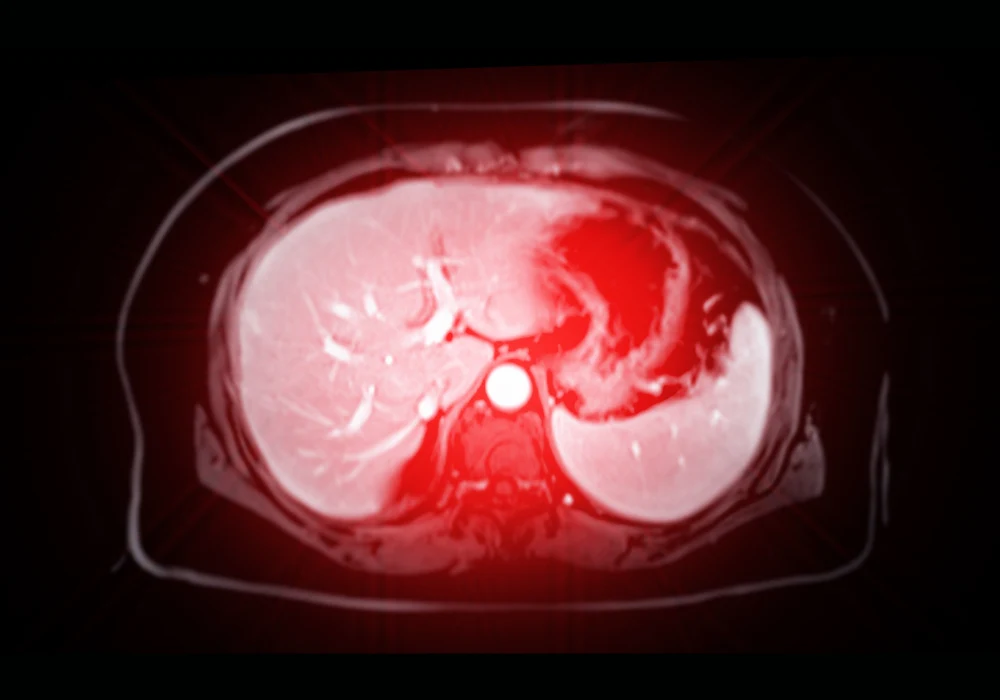

Non-invasive imaging techniques like MRI have shown potential in predicting MVI, particularly when integrated with deep learning methods. However, many existing models suffer from limited generalisability, often due to reliance on single-centre data. To overcome this, a multicentre study developed an interpretable adversarial network-based deep learning (AD-DL) model using MRI data from five centres, aiming to deliver robust MVI prediction and prognostic stratification.

The study retrospectively analysed MRI and clinical data from 546 patients diagnosed with HCC, drawn from five tertiary medical centres. Patient data from three centres were split into training and internal test sets, while two other centres provided external test cohorts. Additionally, transcriptomic data from The Cancer Imaging Archive (TCIA) were used for biological interpretability analysis. The MRI scans followed protocols aligned with AASLD guidelines, and tumour regions were manually segmented across seven MRI sequences: in-phase (IP), opposed-phase (OP), T2-weighted imaging (T2WI), non-contrast phase (NCP), arterial phase (AP), portal venous phase (PVP) and delayed phase (DP).

To enhance generalisability, the AD-DL model was designed using adversarial training strategies. The architecture included a feature extraction module, MVI classifier, hospital classifier and a gradient-reversal layer (GRL) to learn domain-invariant features. The model tested various MRI sequence combinations, with the IP, OP and AP sequence set showing the highest predictive performance.

The AD-DL model's predictions were significantly associated with early recurrence-free survival (ERFS). Among patients in the Taizhou centre, those identified as MVI-positive by the model had a mean ERFS of 14.1 months compared to 20.7 months in the MVI-negative group. Grad-CAM visualisation showed that the AD-DL model focused on tumour margins for MVI-positive predictions, aligning with known pathological observations that most MVI occurs peritumorally.